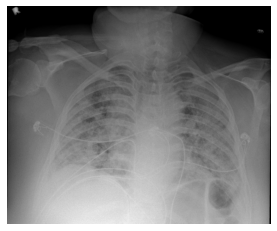

Figure 3 illustrates the frameworks for each of the prediction tasks over the succeeding 24 hours. Figure 3(a) shows an example of SIP predictions from a patient with increased lung opacity. In this case the patient did not suffer any adverse event in the next 24 hours, but ultimately suffered all three adverse events within 72 hours. Figure 3(b) shows an example of ORP predictions from a patient that required increased oxygeen within 24 hours. In Figure 3(c), a sequence of chest X-rays with increasing lung opacity is used by the MIP model to predict COVID deterioration for a patient. The images were taken 49 hours apart. For the case of Figure 3(c), the patient was transferred to the ICU, intubated, and suffered a mortality within 24 hours.

Refer to caption ORP Predictions >6L24: 0.768

(b)

Figure 3: Example model outputs for ICU (ICU24), intubation (Int24) mortality (Mor24), and oxygen greater than 6 L per day (>6L24) prediction tasks, all at 24 hours. (3(a)) Example SIP outputs based on a single image with evident increased lung opacity. In this case the patient did not suffer any adverse event in the next 24 hours, but would ultimately suffer all three adverse events within 72 hours. (3(b)) Example ORP output based on a single image. This patient required greater than 6 L per day of oxygen within 24 hours. (3(c)) Example MIP outputs. Both images were taken from the same patient with 49 hours of separation. Increased lung opacity is observable in the second (later) image. The patient suffered all three adverse events within 24 hours.